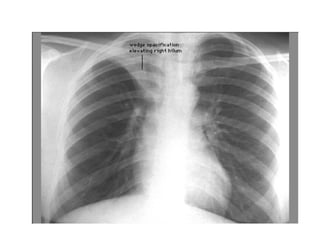

Chest x ray

Finally, Check the Lung Fields

• Infiltrates

• Increased interstitial markings

• Masses

• Absence of normal margins

• Air bronchograms

• Increased vascularity